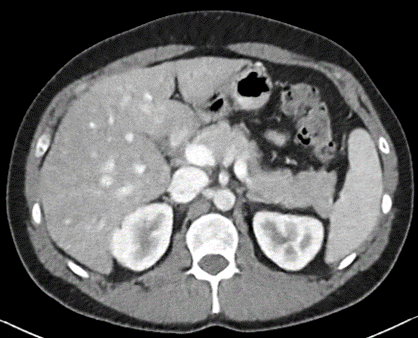

Figure 2: Comparison of generated Pseudo-LDCT images and their noise. (a) LDCT, (b) Random noise histogram, (c) Gaussian noise, (d) Ours. The right-bottom patch indicates the noise lying on each image. The noise quality of (b) and (c) shows that random noise cannot represent (a). In contrast, (d) shows almost similar to (a)

For evaluation, the 2016 AAPM Low-Dose CT Grand Challenge dataset[16] was used and split into 3 train and 7 test, respectively. It consists of abdominal LDCT and NDCT images obtained from 10 patients with image size 512×512512512512\times 512. The voxel space of CT images is 0.5mm×0.5mm0.5𝑚𝑚0.5𝑚𝑚0.5mm\times 0.5mm with 3mm3𝑚𝑚3mm slice thickness. To demonstrate that our method works with any existing learning method, we applied our method to N2C (Noise2Clean), N2N (Noise2Noise)[13], and N2V (Noise2Void)[11]. N2C is a supervised learning method that uses all available labeled paired data. N2N and N2V are self-supervised learning methods which use noisy pair images and masking schemes. Also, to demonstrate the effectiveness of our noise model, we compared LDCT denoising performance against existing noise generation techniques i.e. Random Noise histogram (Hist), Gaussian noise (Gaussian), and Single noise model++Noise histogram (Model+Hist). Hist samples noise from the difference map based on the histogram between LDCT and NDCT images, whereas gaussian samples the noise from a Gaussian distribution with zero mean and 0.02 standard deviation. Model+Hist is the combination of a single pre-trained LDCT noise model (using all subjects in the training dataset) and Hist. For evaluation, Peak Signal-to-Noise Ratio (PSNR) and Structural Similarity (SSIM) are reported.

For parameter updates, it is crucial to generate high-quality Pseudo-LDCT images i.e. images similar to an actual LDCT image. If high-quality Pseudo-LDCT images are provided to the model for training, CT denoising performance can be improved. In contrast, using low-quality Pseudo-CT images may adversely affects the model learning, and consequently lead to decreased denoising performance. Table. 1 also shows the average PSNR and SSIM in different Pseudo-CT image generation settings. Here, both Hist and Gaussian reported lower performance compared to N2C. Based on our observations, this serves to show that random noise employed in natural images is not useful for CT denoising. In contrast, when our noise model was combined with Hist i.e. Model+Hist, performance gains over N2C were noted. This implies that our noise model can generate reasonable noise similar to the actual CT noise, and also improves performance. Furthermore, our ensemble noise models without parameter update show improved results over Model+Hist without the need for additional random noise.

In Figures 2 and 3, we show comparison results of Pseudo-LDCT images and their generated noise using various methods, as well as the predictions of our method for each. In Fig. 2, Pseudo-LDCT images and their noise with Hist and Gaussian highlight a huge discrepancy between the actual LDCT image and its noise. In the case of random noise that is shown to be independently distributed across the entire image, it is often useful for natural image denoising. Moreover, this types of noise does not accurately reflect the nature of CT images. Through the proposed method, we show it is possible to generate Pseudo-CT images that preserve overall CT image characteristics with high quality (Fig. 3).